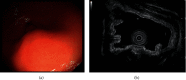

In this report, we describe a patient with myoepithelial hamartoma, which is regarded as synonymous with adenomyosis and heterotopic pancreas. Endoscopy revealed a submucosal tumor in the antrum of the stomach. Subsequently, distal gastrectomy with Roux-en-Y reconstruction was performed. Histological findings of adenomyomatous lesion and heterotopic pancreatic tissue were observed in this lesion. The distribution of OCT4, which is a pluripotency marker, varied in each part.